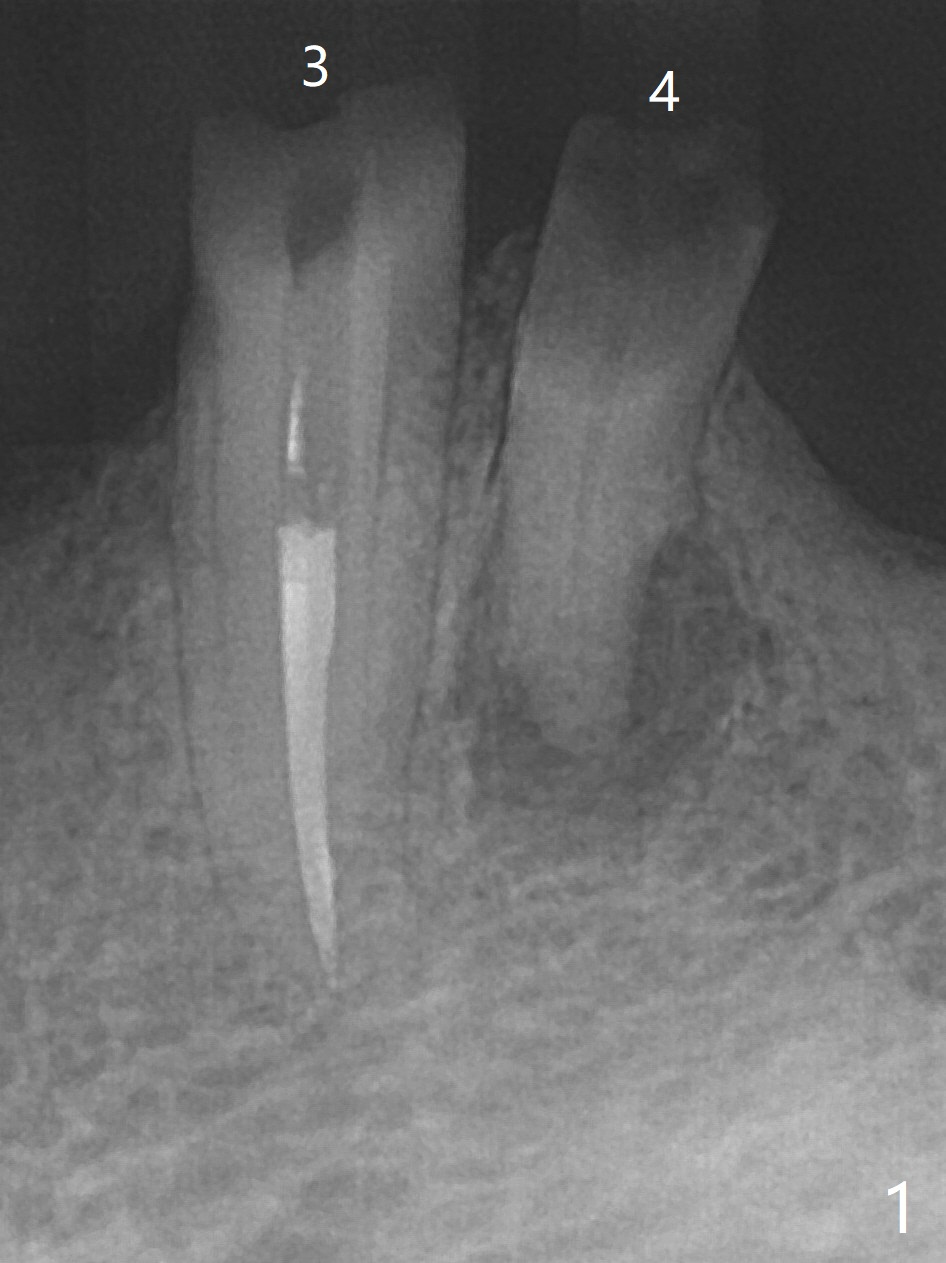

68女五年前戴上上颌全口假牙,下颌局部托牙(由左下3牙冠/桩,右下3,5支撑),最近失去牙冠/桩(图一),终于同意左下4种植 (4x11.5 mm)/球状基台(图二),左下3放置球帽。